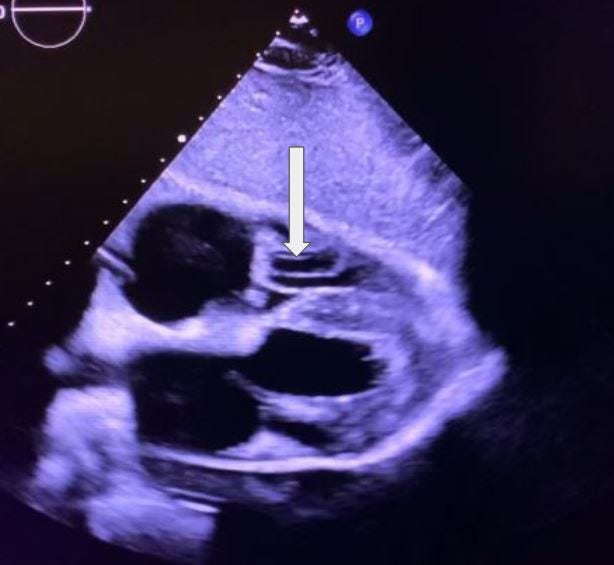

What section of the aorta is the arrow pointing to in this 3-chamber view?

A. Aortic Root

B. Descending aorta

C. Abdominal aorta

D. Aortic Arch